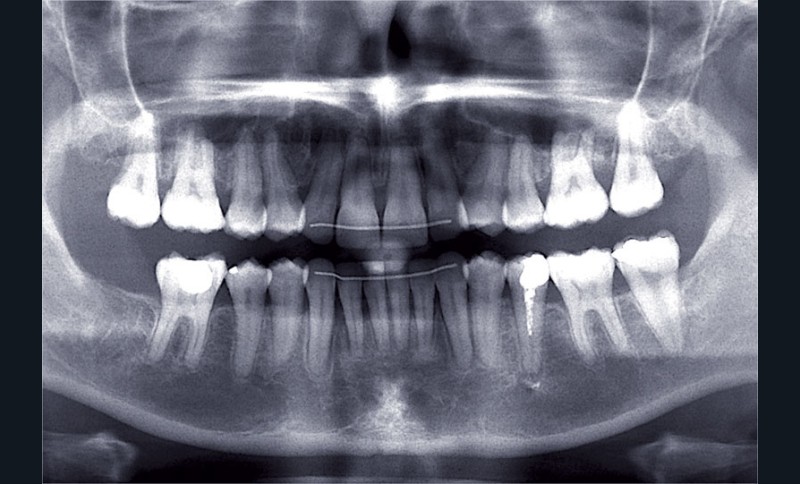

Nous lui avons donc proposé un traitement d’alignement avec maintien des 14 et 24 en position de 13 et 23 et optimisation du torque pour favoriser un développement des arcades et chercher à améliorer le sourire et le soutien labial.

Un appareillage Damon métal a été mis en place, réalisé à partir d’un set up numérique Insignia pour obtenir un contrôle précis des torques et de la forme d’arcade et réduire le temps de finition grâce à un collage indirect très précis.

De larges surélévations postérieures étalées ont été mises en place et la patiente a porté des élastiques précoces suivant les principes de la technique Damon. Les 14 et 24 rempliront le rôle des 13 et 23.

L’objectif, en utilisant la technique Insignia est de réduire le temps de traitement de 28 à 18 mois avec 12 rendez-vous (fig. 5 à 14).